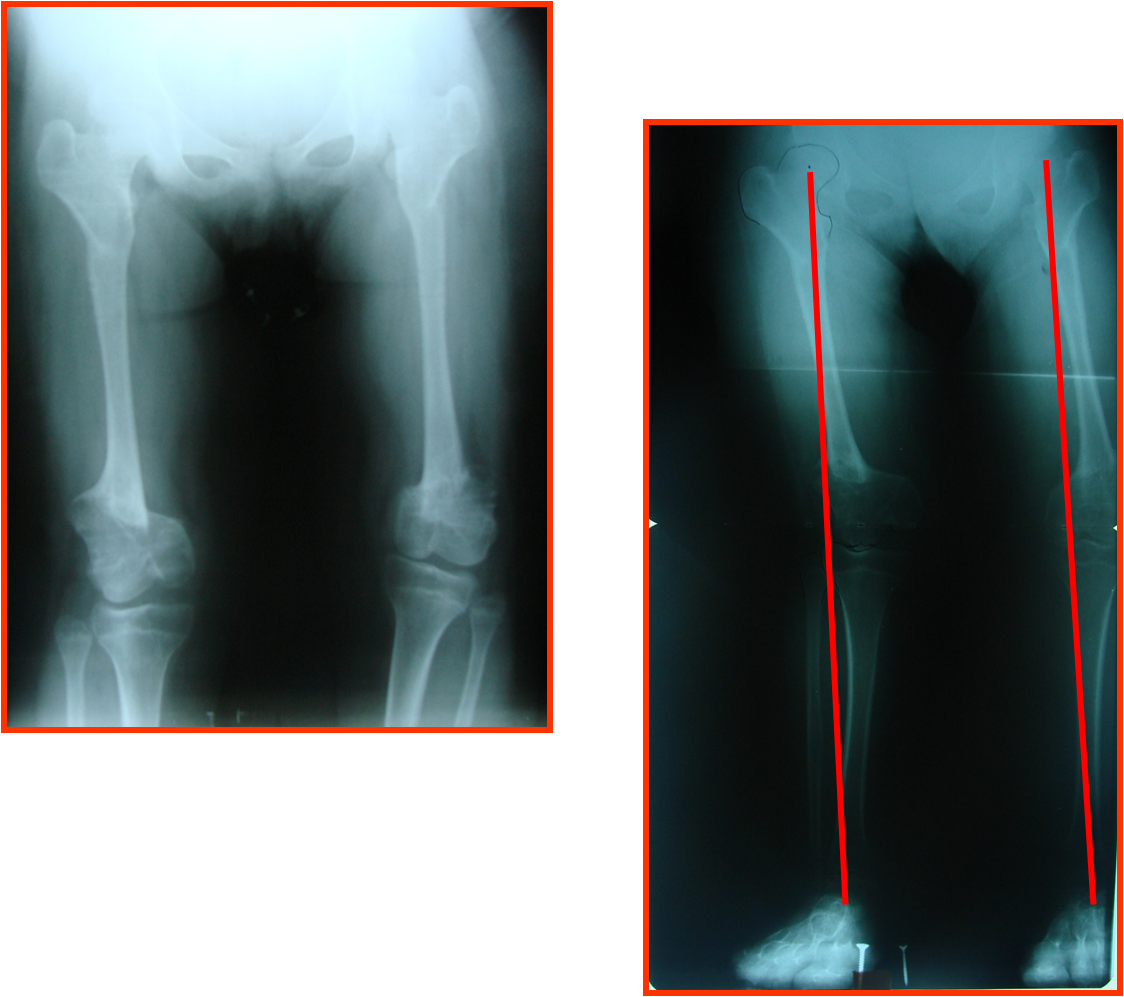

arthritis deformity surgery endoprosthesis hip prosthesis ilizarov ilizarov surgery infected nonunion knee prosthesis lengthening surgery limb lengthening surgery nonunion periprosthetic infection psodoartroz revision surgery total hip prosthesis total knee prosthesis